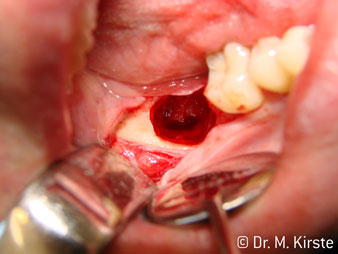

Le contre-angle avec tête angulée à 45° a surtout été choisi pour ses nombreux avantages. Les collègues qui exercent en chirurgie, et à qui cet instrument est principalement destiné, apprécieront très vite la possibilité de travailler efficacement dans des zones très étroites. En particulier, lors d’extractions de dent de sagesse (Ill. 2), où il n'y a pas besoin d’un grand angle d’écartement des tissus mous dans la région de la joue (Ill. 3). Pendant la préparation, une légère rotation de la tête de l’instrument permet un travail rapide et sans risque dans la zone rétromolaire.

Ill. 2

Ill. 3